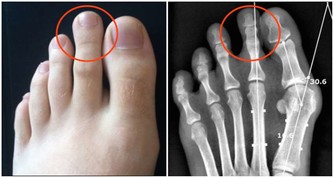

4、腹部包塊

腫塊質硬,形體不規則,可隨腸管有稍微的活動度,晚期時侵潤較甚,腫塊可固定不。